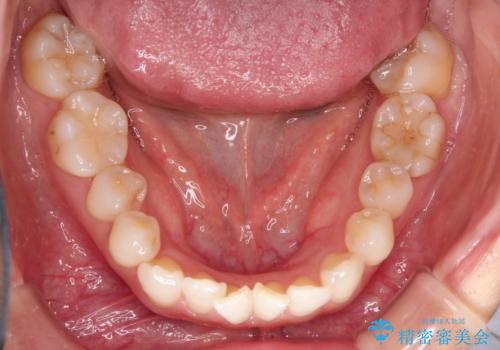

八重歯と前歯のガタガタをインビザラインで

- 八重歯と前歯のガタガタを主訴に来院されました。

目立たず矯正したいとのことでインビザラインで矯正することとしました。